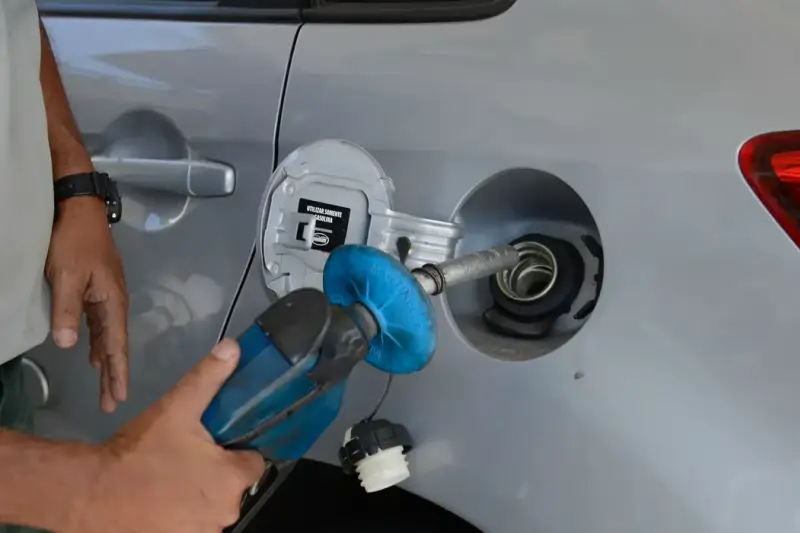

Inalação do vapor de gasolina causa câncer e ameaça frentistas